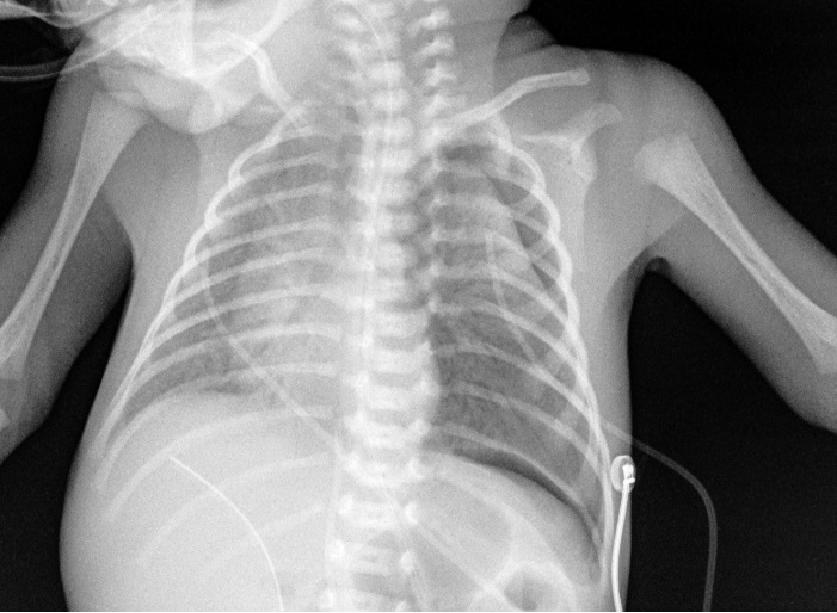

可有合并症:早产儿呼吸窘迫综合征机械通气1天后合并气胸

第2天X线,可见左侧气胸